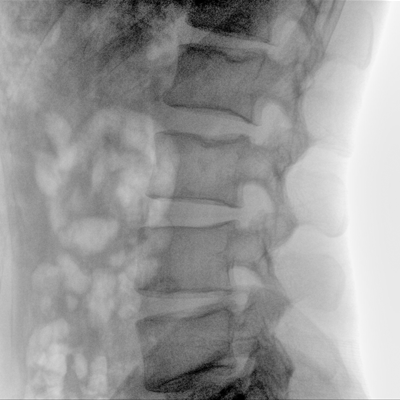

骨科: 經(jīng)皮錐體成形術(shù)、經(jīng)皮椎間盤臭氧治療術(shù)、胸脊椎固定、骨活檢、腰椎內(nèi)固定術(shù)等。

優(yōu)質(zhì)平板探測(cè)器、可靈活升降調(diào)節(jié)SID、獨(dú)特圖像處理系統(tǒng)、高品質(zhì)濾線柵,大視野成像清晰不失真。